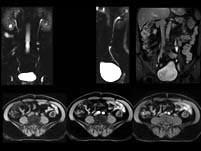

问题 男,57岁,无痛性肉眼血尿2个月,MRI检查如图所示,下列说法错误的是 ( )

选项 A、左侧输尿管管壁节段性增厚,提示输尿管癌 B、考虑为左侧输尿管炎 C、左侧输尿管中段管腔内可见软组织信号影 D、左侧输尿管中段内的软组织信号影,增强后有轻度强化 E、左侧输尿管中段可见充盈缺损表现

答案 B